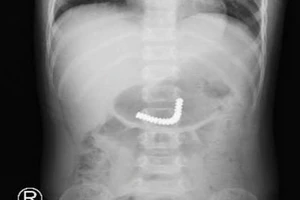

Cắt, nối ruột cho 2 bé trai nuốt 38 viên nam châm